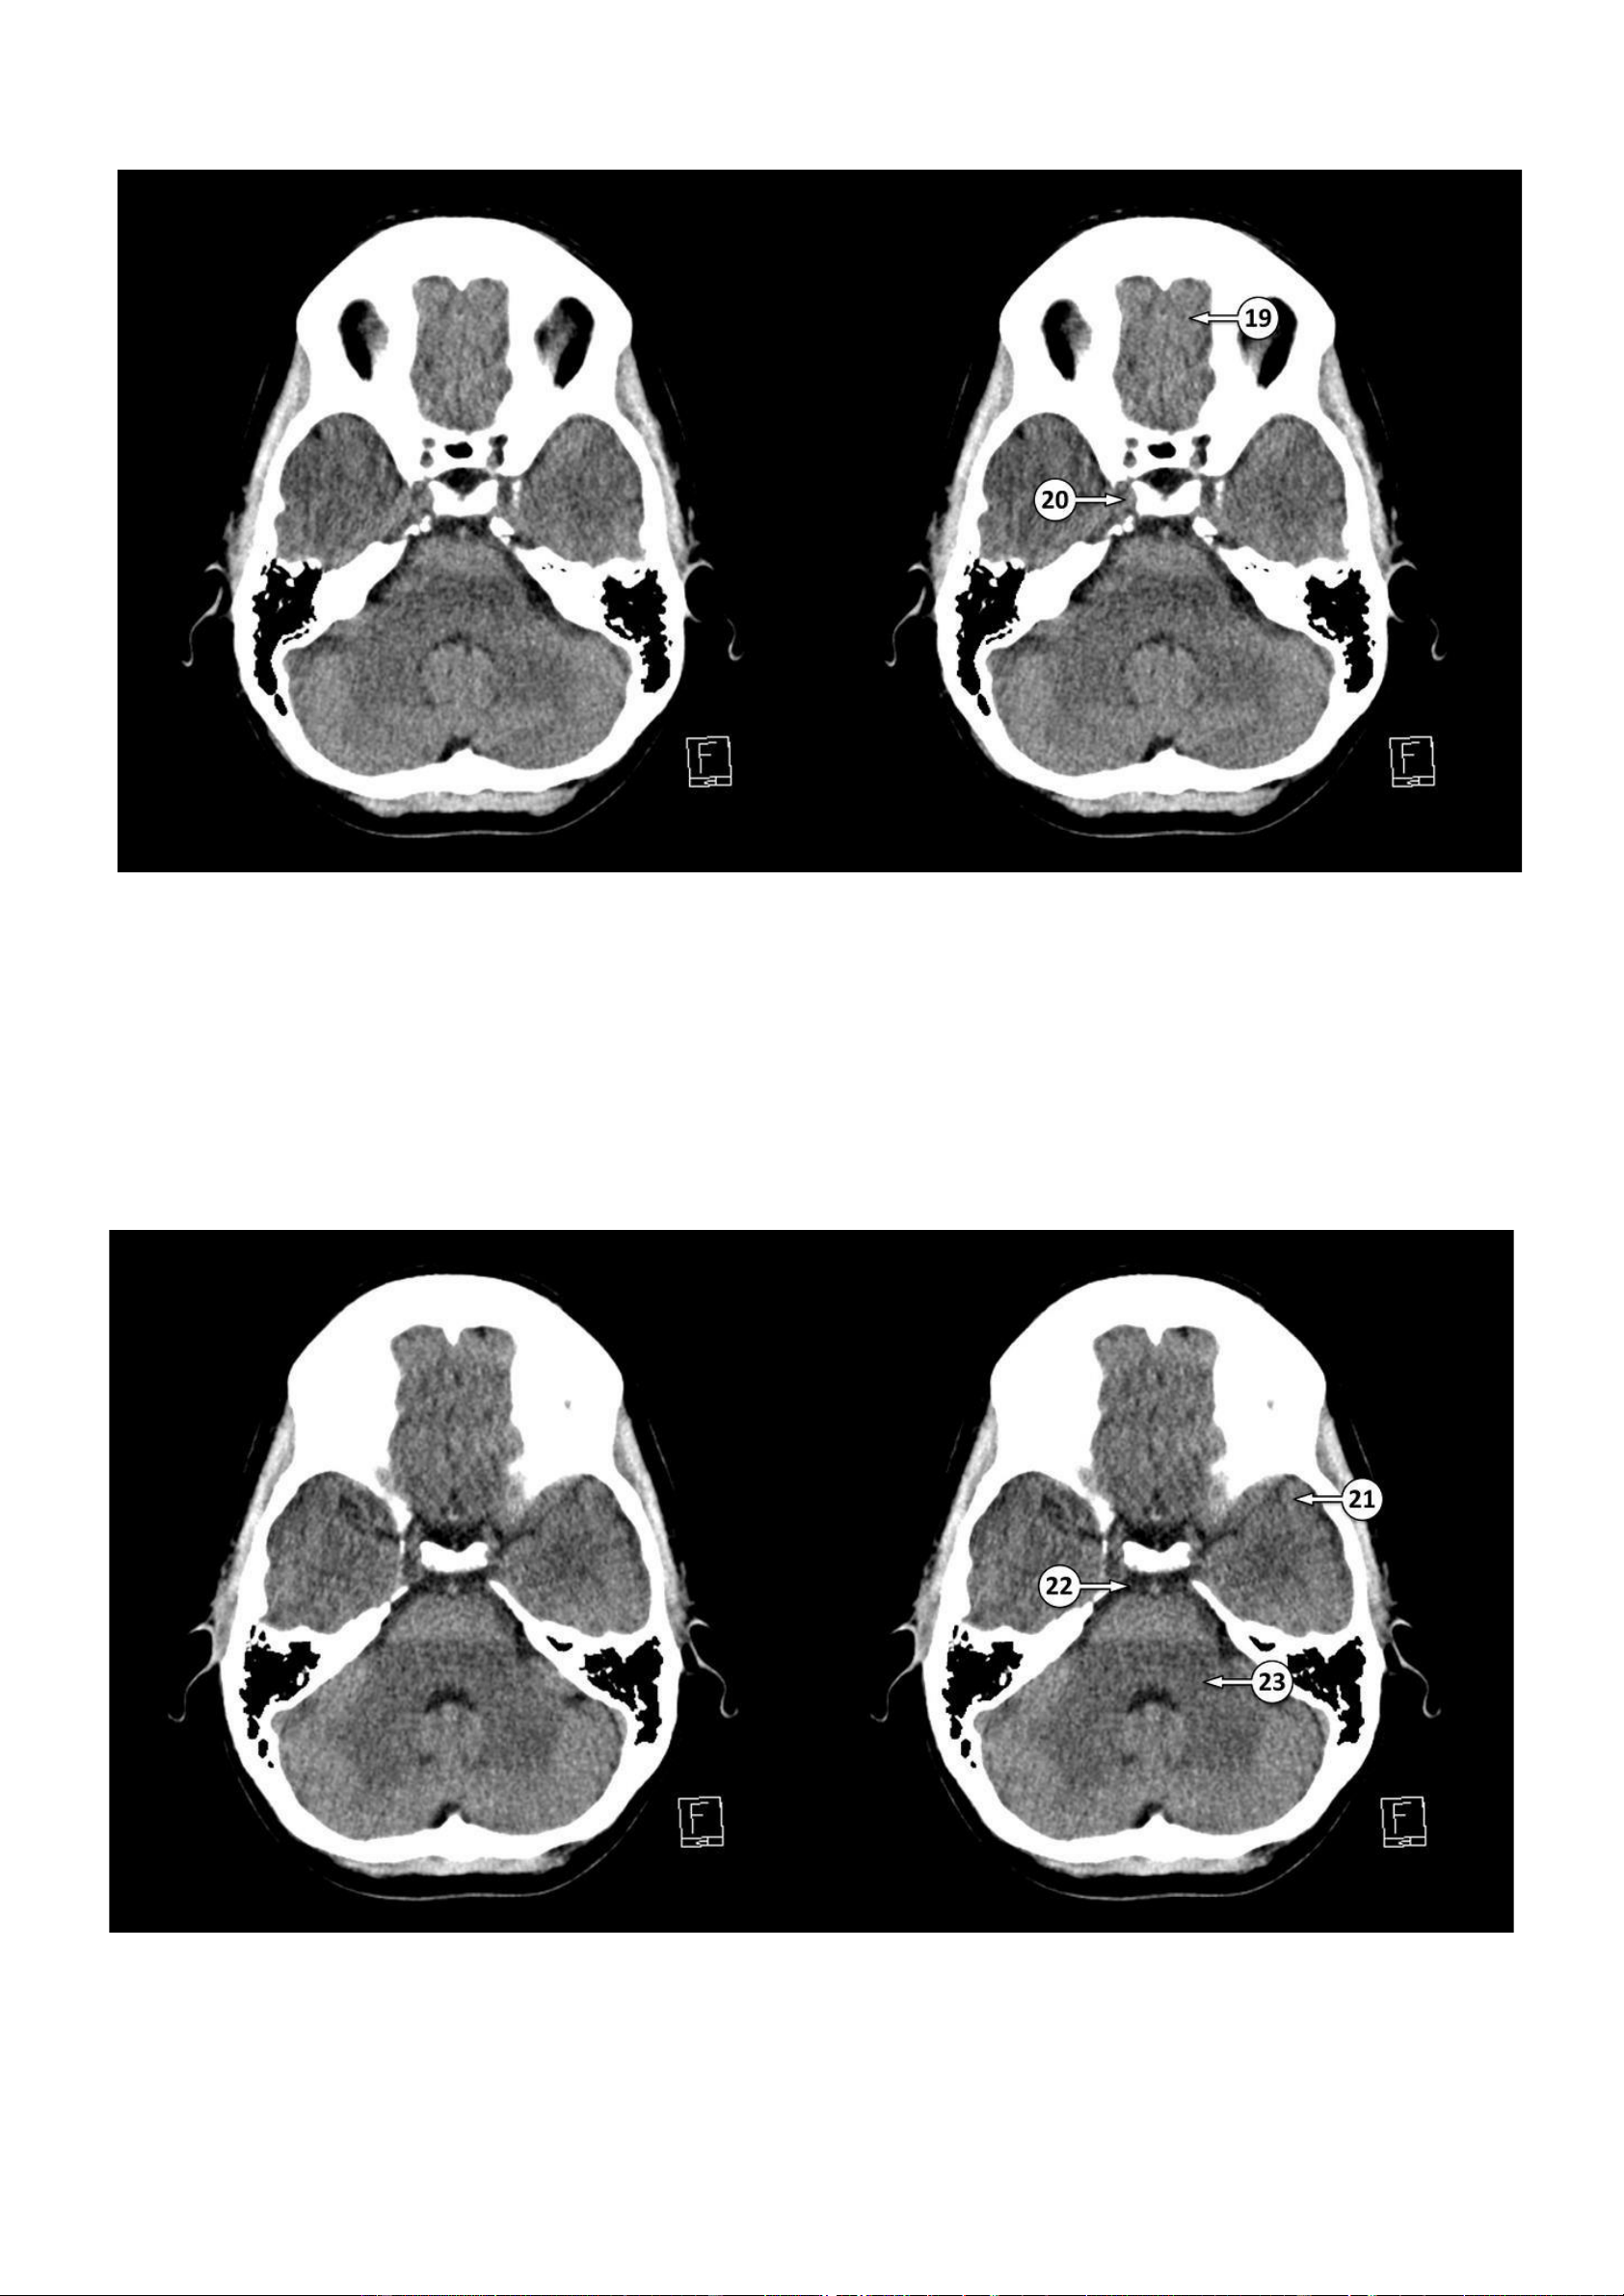

Thảo Thảo & Bé Nghìn Dặm ▪ Số 19: Hồi thẳng

▪ Số 20: Động mạch cảnh trong đoạn xoang hang nằm trong xoang hang 21: Cực thái dương 22: Bể trước cầu não

23: Cuống tiểu não giữa lOMoAR cPSD| 22014077